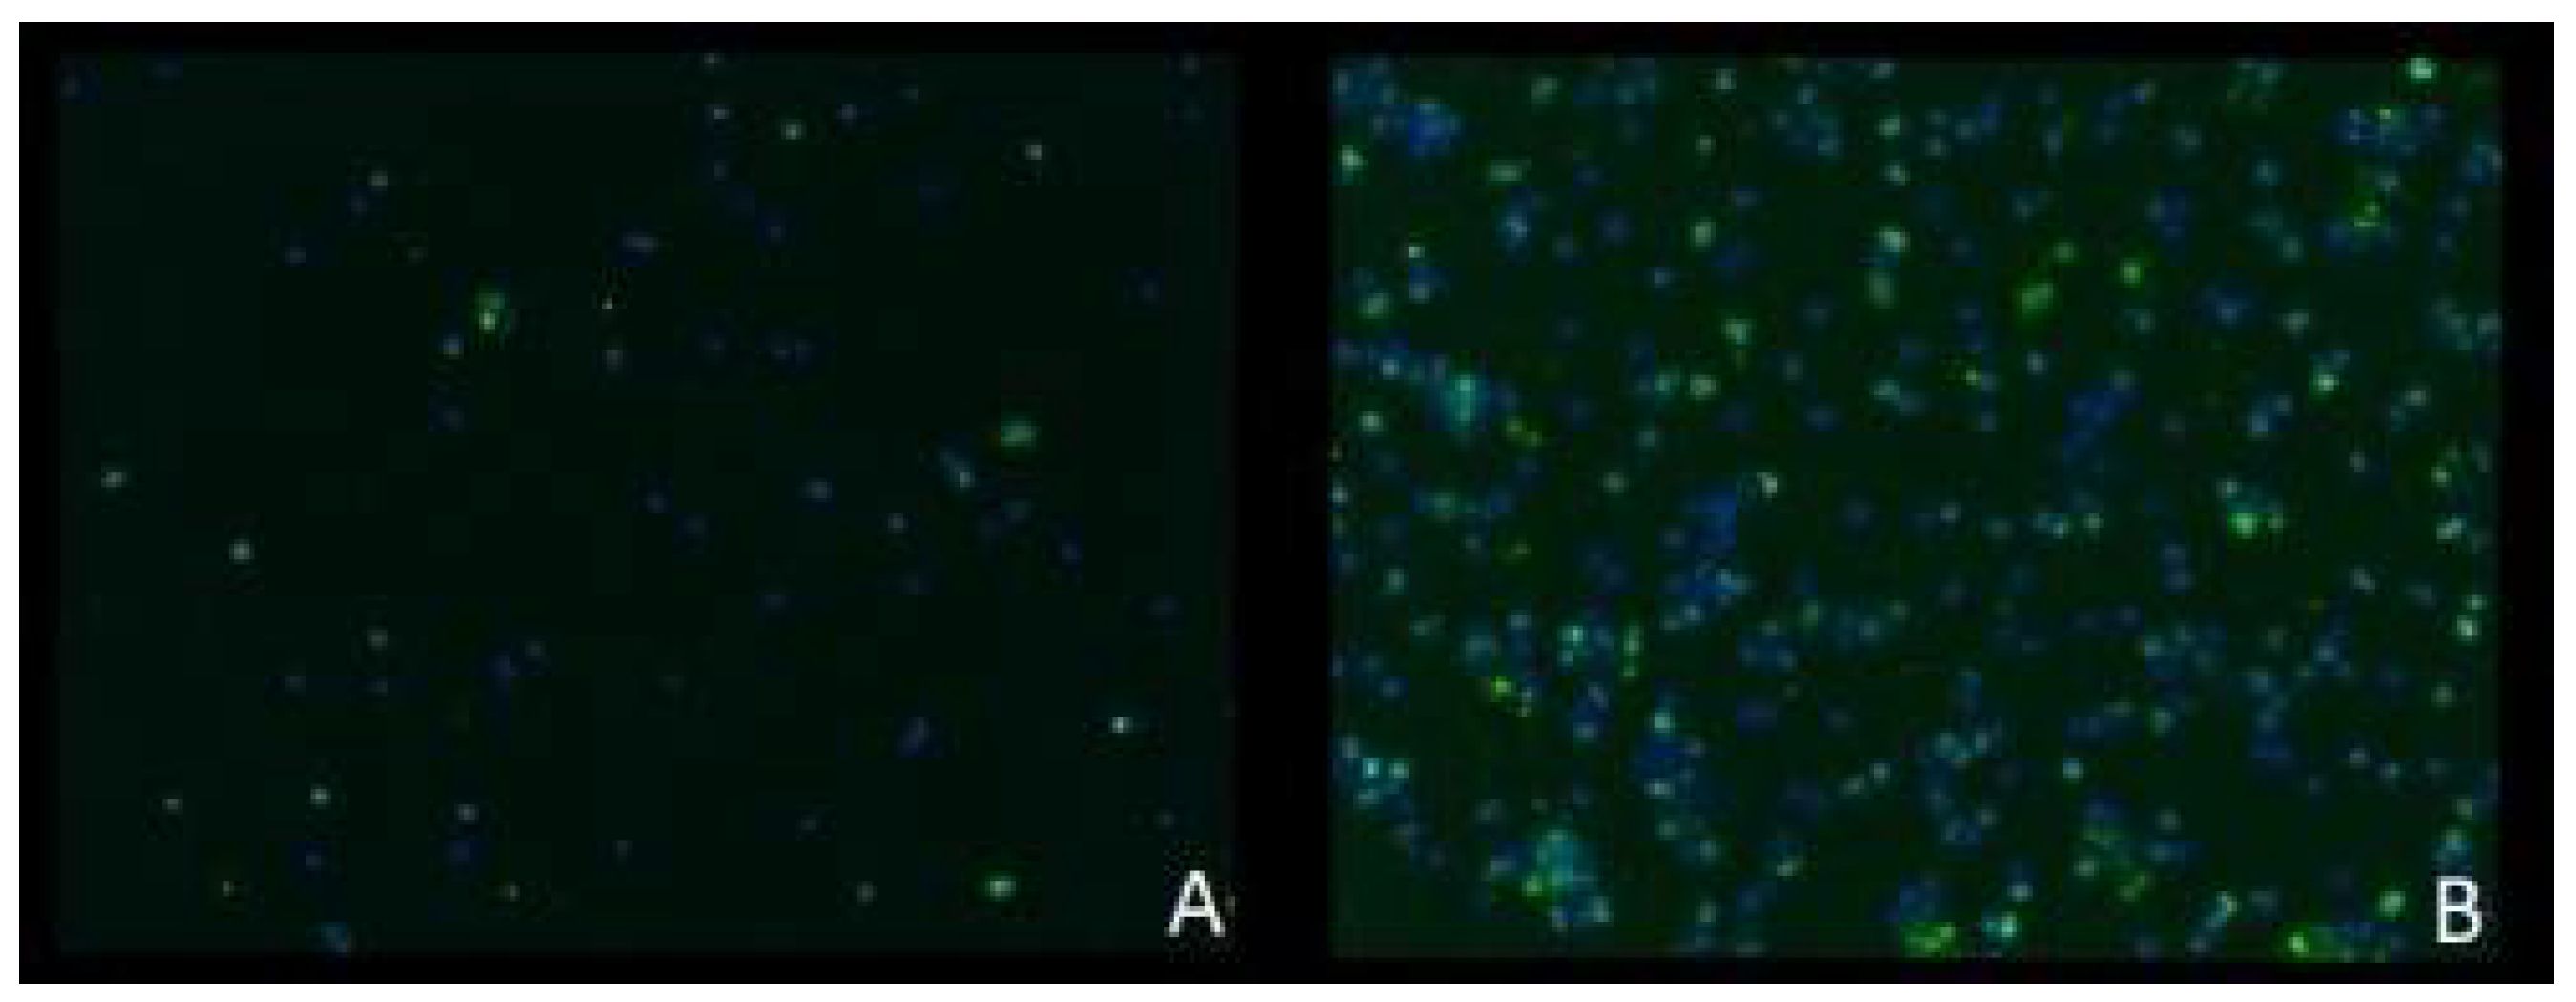

3.4. Staining of Double-Strand Breaks